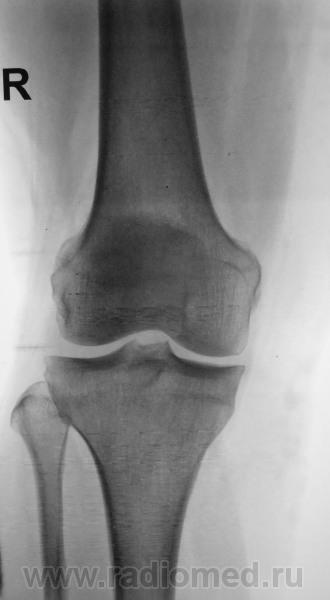

Незначительное сужение в медиальном отделе+уплощение и субхондральный склероз суставных поверхностей+заострение межбугорковых возвышений+уплотнение собственной связки надколенника= Остеоартроз I ст. Возможно добавил тенденит еще

доа 1 стопроцентный.